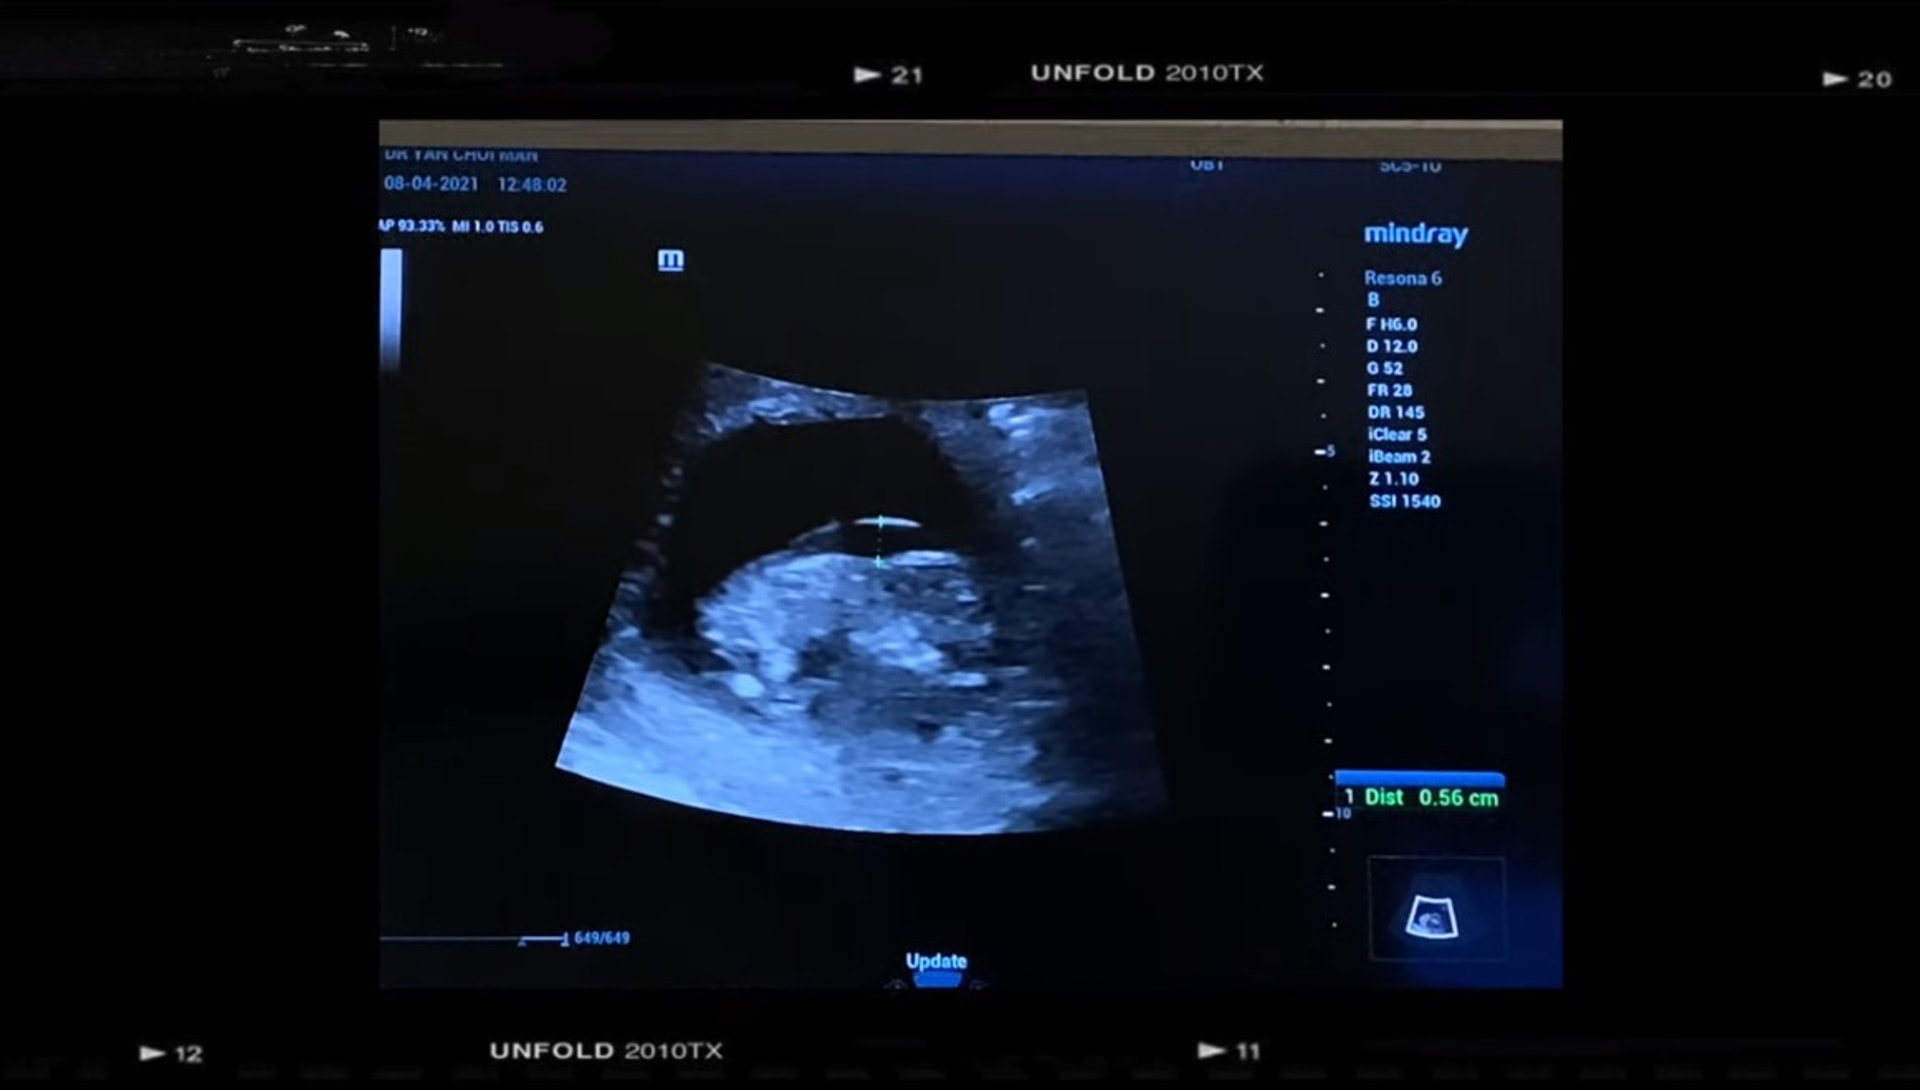

Leanne 第3次懷孕時,被醫生告知胎兒的頸皮厚,要驗血做T21。Leanne 憶述當時情況「醫生解釋:頸皮有5.5厚,要驗血做T21,頸皮厚可以反映唐氏or 心臟問題。聽完之後我整個人迷失了。等報告的一星期每日除了喊,就是上網看其他媽媽的經歷,事後我跟丈夫商量如果胎兒是唐氏綜合症都會選擇生下孩子,我們有能力照顧孩子和給孩子無限的愛。」

可惜驗血後,胎兒並沒有唐氏綜合症,反而得了更嚴重的「 愛德華氏症 」。Leanne表示,「當上網搵資料嘅時候,我彷彿靈魂出竅,為什麼會發生我身上。愛德華氏症根本是沒有希望的病。很大部份機會胎死腹中,就算可以出世,都是得幾分鐘或者幾個鐘或者幾個月。莫非上天真的不想我擁有你?我們已經接受唐氏,怎料還有更壞嘅打算。在等待抽絨毛的幾天,每天我猶豫傻婆一樣,一直在網上看資料,看其他媽媽翻盤的資料,因為我還想保留一點點希望。原來也有很多像我這樣個案,但最後醫生照早期結構,和絨毛翻盤的資料。抽的日子到了,一路安慰自己,到見醫生的時候,醫生都說有可能抽錯的。」

醫生說有可能抽錯,Leanne 還是心存希望。可惜現實總是殘酷,Leanne 憶述當時情況,「醫生說「唔好意思!」你的BB是愛德華氏樣。BB的左右腦沒有分左右,心有嚴重的問題,沒有鼻骨,腸外露,手少了一隻骨,腳也是彎的。還有很多很多問題!醫生建議不用抽絨毛。雖然已經好肯定是愛德華氏,就算不是,也是一個畸胎,有非常嚴重的問題。所以我哋最後沒有抽。」